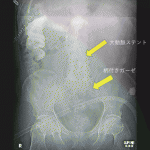

手術終了時のガーゼカウントは合致しており,術後のレントゲン写真では大動脈ステントグラフトに重なったガーゼが見逃されていた(図1).長時間手術後に撮影したレントゲン写真で,プロトコール通り2名で確認はされていた.手術は肝切除後の13番付近のリンパ節サンプリング部で出血があり,ガーゼで押さえていたシーンもあった.ガーゼカウントが合致している状況で,疲労した外科医が他の遺物とのオーバーラップを指摘するのは至難の業と思った.